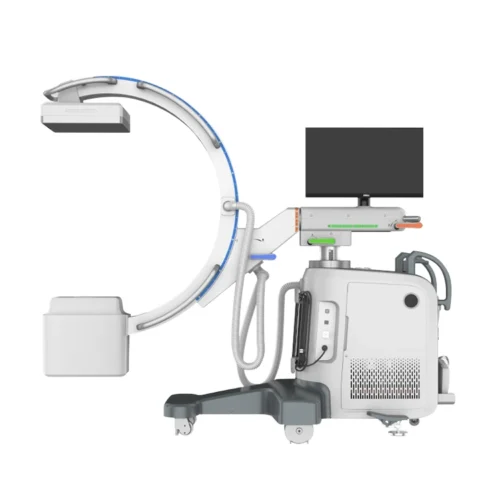

CFV-CM605V Veterinary C-arm System